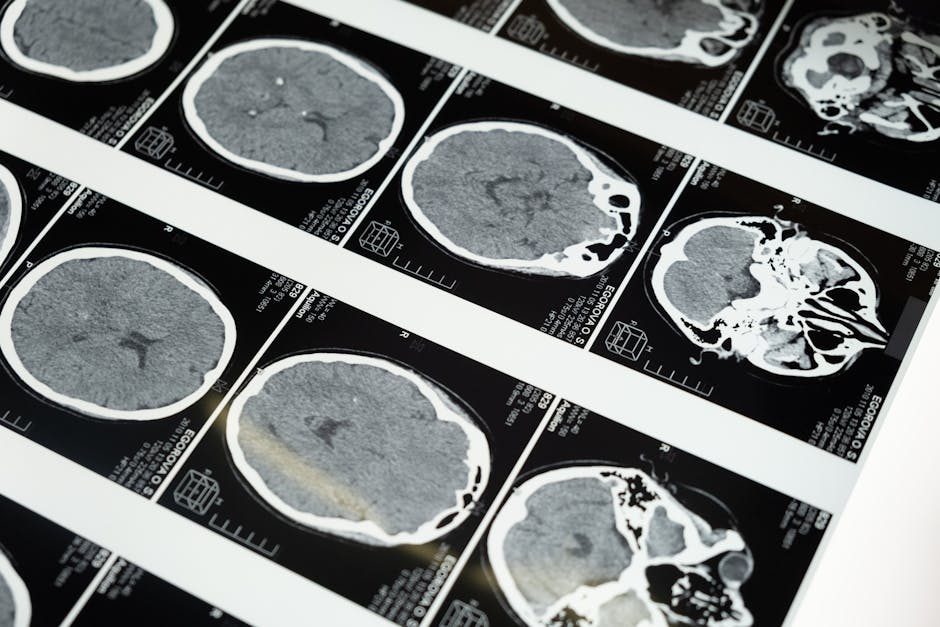

Renal Clearance and Kidney Function Timelines

Because iodine contrast is primarily cleared through the renal system, the health of the kidneys is the most significant factor in the elimination timeline. Contrast-Induced Acute Kidney Injury (CI-AKI) is a temporary decline in renal function that follows a specific, predictable clinical path.